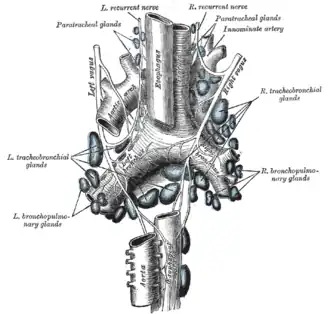

The tracheobronchial lymph glands. | |

These lymph nodes form four main groups including paratracheal, tracheobronchial, bronchopulmonary and pulmonary nodes.

- Paratracheal nodes are located on either side of the trachea.

- Tracheobronchial nodes can be divided into three nodes including left and right superior tracheobronchial nodes, and the inferior trachiobronchial node. The two superior tracheobronchial nodes are located on either side of trachea just before its bifurcation. The inferior tracheobronchial node is located just below the bifurcation in the angle between the two bronchi.

- Bronchopulmonary nodes (hilar nodes) situate in the hilum of each lung.

- Pulmonary nodes are embedded the lung substance on the larger branches of the bronchi.

The afferents of the tracheobronchial glands drain the lungs and bronchi, the thoracic part of the trachea and the heart; some of the efferents of the posterior mediastinal glands also end in this group.

Their efferent vessels ascend upon the trachea and unite with efferents of the internal mammary and anterior mediastinal glands to form the right and left bronchomediastinal trunks.